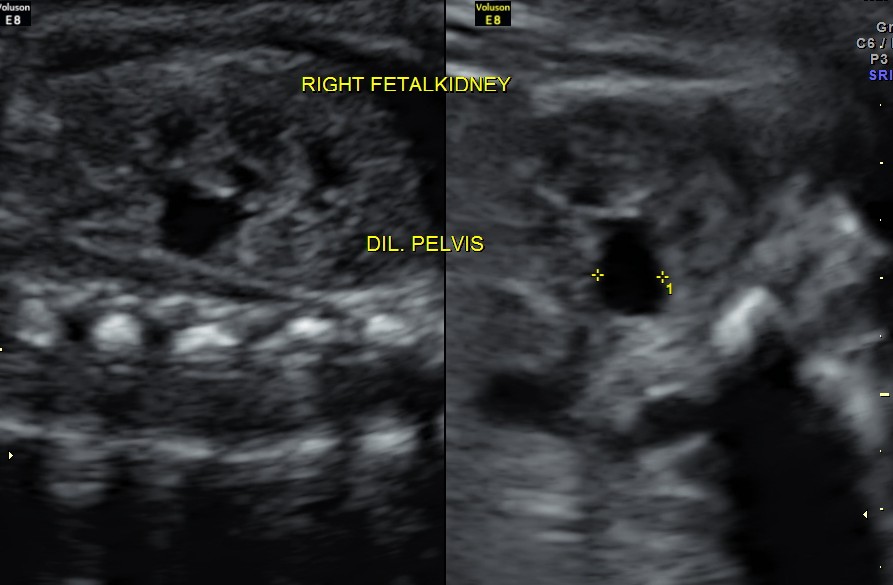

The following images show bilateral renal pelvi ectasis and bilateral dilated ureters with all the changes more in the left kidney .

Axial images of kidney would better showed the urethral dilation